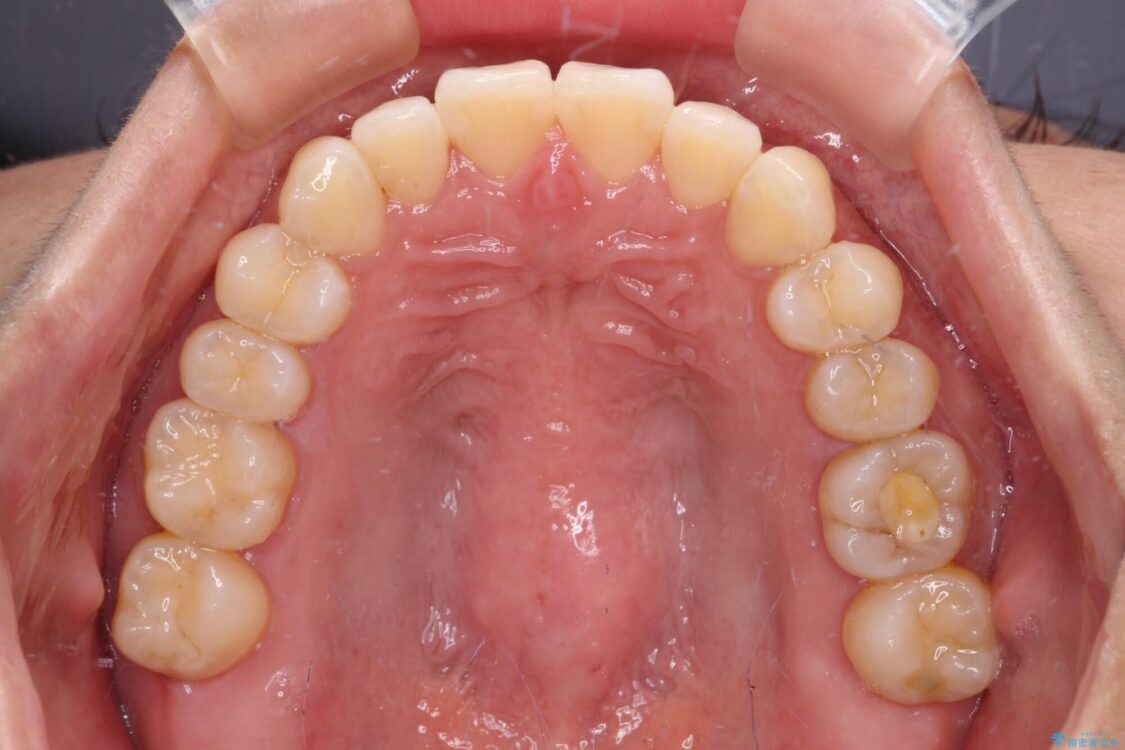

治療後について

装着時間を守ってくださったので、予定通りの期間で終えることができました。インビザライン特有の、奥歯の咬み合わせの問題もなく、しっかりと歯列を改善することができました。

治療後

• 【モニター】前歯のデコボコをインビザラインで改善 治療後画像